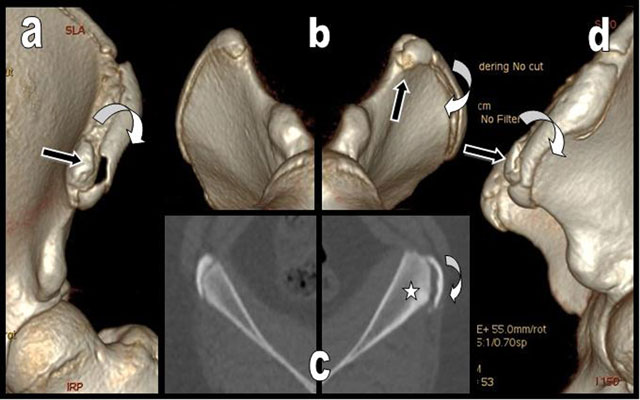

Figure 2

Left anterior (a), comparative right and left oblique inferior (b) and left lateral (d) 3D CT reconstructions of the left iliac crests illustrate the avulsion of the anterior part of the left iliac crest apophysis. It is displaced outwardly and downwardly (curved white arrow) but the apophysis of the anterior and superior iliac spine - origin of the sartorius - is respected and not displaced (black arrow). Comparative axial views of the right and left iliac crests (c) show preexisting hypertrophy and bony sclerosis of the left parent iliac bone due to chronic overuse (white star).